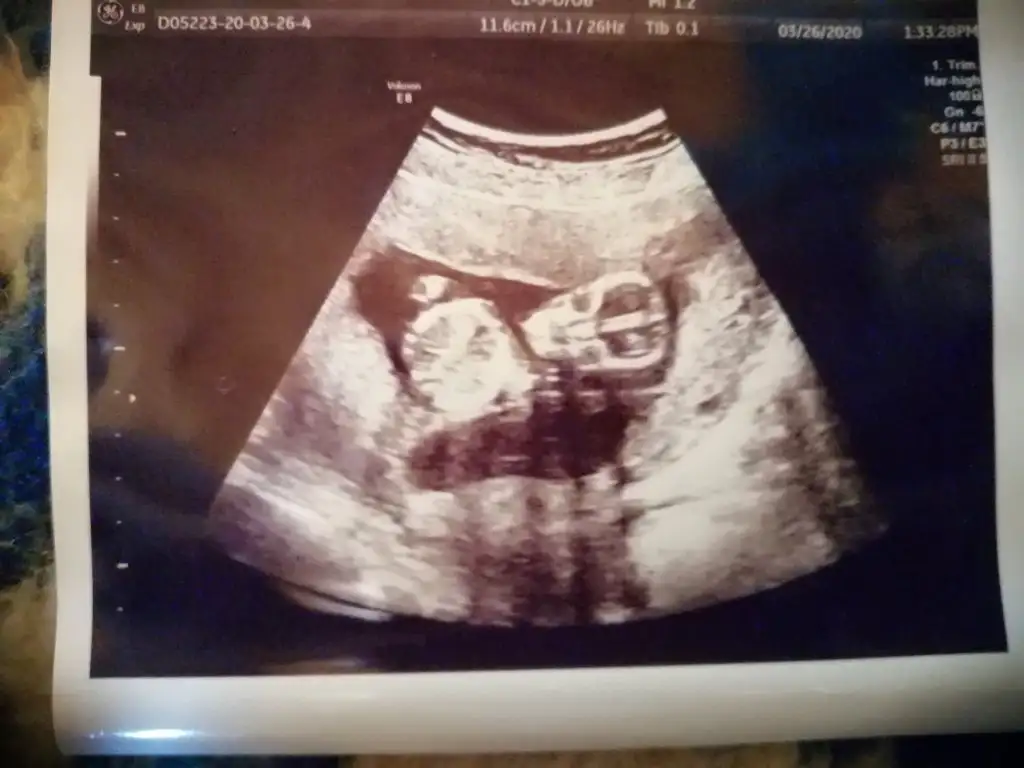

ay bende çok merak ediyorum 14haftalık usg bu acaba kız mı erkek mi olacak 😊 doktor bacaklarını açmıyor dedi 2 hafta sonrada çağırdı kesin Konuşuruz dedi ama ben duramıyorum meraktan

Nubu net değil sanki erkek gibi bilemedim ben 11 12 13 haftalara bakıyorum 14 de organı oluşuyor çunki

burdan bellimi bisiler, ultrsn kagidindan belli degil demistin,13 haft.bu sonradan aklima geldi bunu atmak 😊😊

Oglum var bitane 5 yasinda.enn onemlisi saglikli olmasi benm bnm icin elbette, merak iste kizdir belki diye kontrolüme de var bi 20 gun falan.

Diger usg de tam hatırlamıyorum sanki kız gibi demiştim